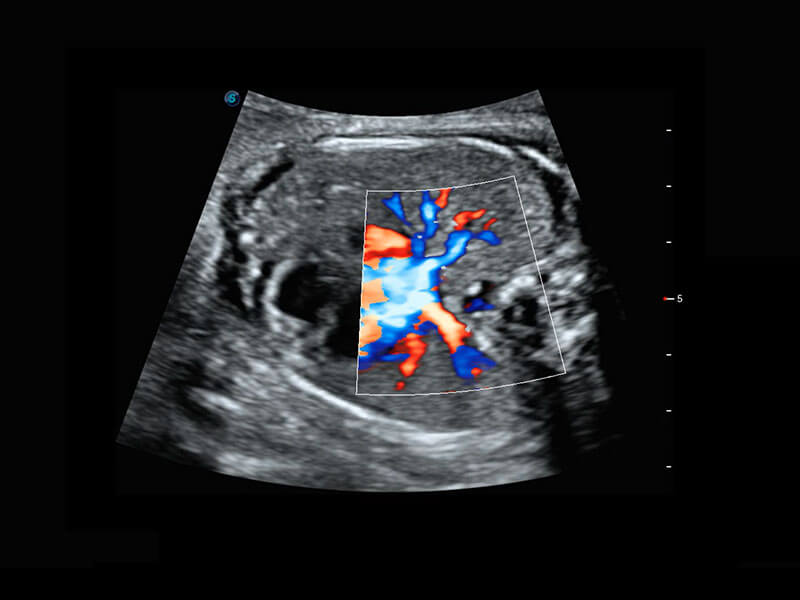

P60搭載一系列胎兒心臟成像技術(shù),實(shí)現(xiàn)精細(xì)的胎兒心臟評(píng)估。

四腔心血流